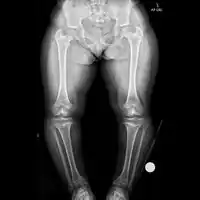

Radiologic findings

A skeletal survey is useful to confirm the diagnosis of achondroplasia. The skull is large, with a narrow foramen magnum, and relatively small skull base. The vertebral bodies are short and flattened with relatively large intervertebral disk height, and there is congenitally narrowed spinal canal. The iliac wings are small and squared, with a narrow sciatic notch and horizontal acetabular roof.[15][16] The tubular bones are short and thick with metaphyseal cupping and flaring and irregular growth plates.[15] Fibular overgrowth is present. The hand is broad with short metacarpals and phalanges, and a trident configuration. The ribs are short with cupped anterior ends.[15] If the radiographic features are not classic, a search for a different diagnosis should be entertained. Because of the extremely deformed bone structure, people with achondroplasia are often "double jointed". The diagnosis can be made by fetal ultrasound by progressive discordance between the femur length and biparietal diameter by age. The trident hand configuration can be seen if the fingers are fully extended.

Another distinct characteristic of the syndrome is thoracolumbar gibbus in infancy.